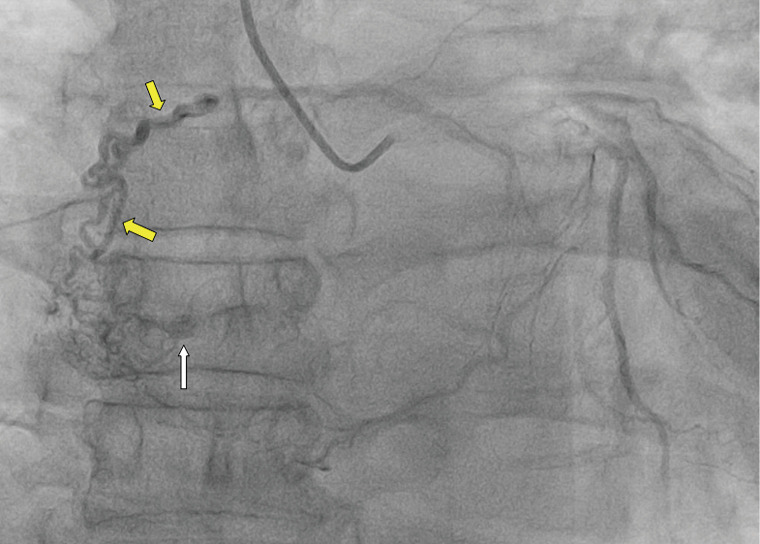

Left atrial myxoma complicated by a coronary artery fistula due to rupture of the feeding artery: a case description.

左房黏液瘤并发供血动脉破裂致冠状动脉瘘1例。